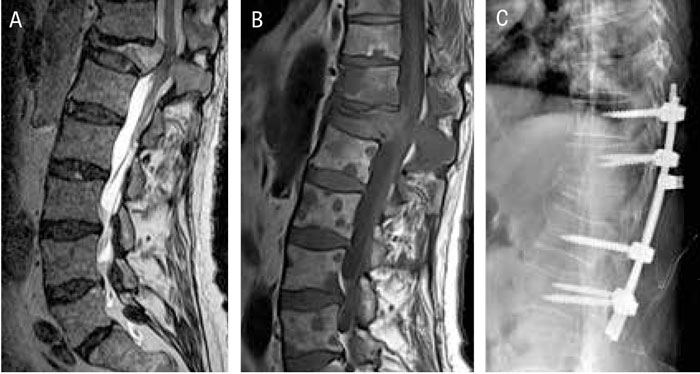

Patient med kotmetastaser där tumörväxt i Th 12 lett till kompression av kotan: A) Sagittal MRT-bild med T2-sekvens, där Th 12 tydligt är komprimerad, buktar bakåt och medför påverkan på ryggmärgen/conus i denna nivå. B) Sagittal MRT-bild med T1-sekvens visar multipla mindre tumörförändringar i samtliga kotor och i spinalutskott Th 11 och Th 12. C) Postoperativ slätröntgenbild efter operation med dekompression och fixation.